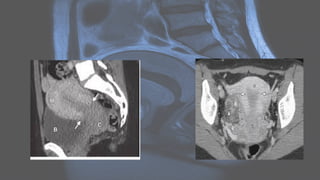

CT IMAGING

• tubular adnexal "mass"

• fallopian tube thickening of >5 mm with enhancing wall: has high specificity of 95%

• indistinct uterine border

• thickening of the uterosacral ligaments

• complex free fluid in the pouch of Douglas (cul-de-sac)

• pelvic fat stranding or haziness

• reactive lymphadenopathy